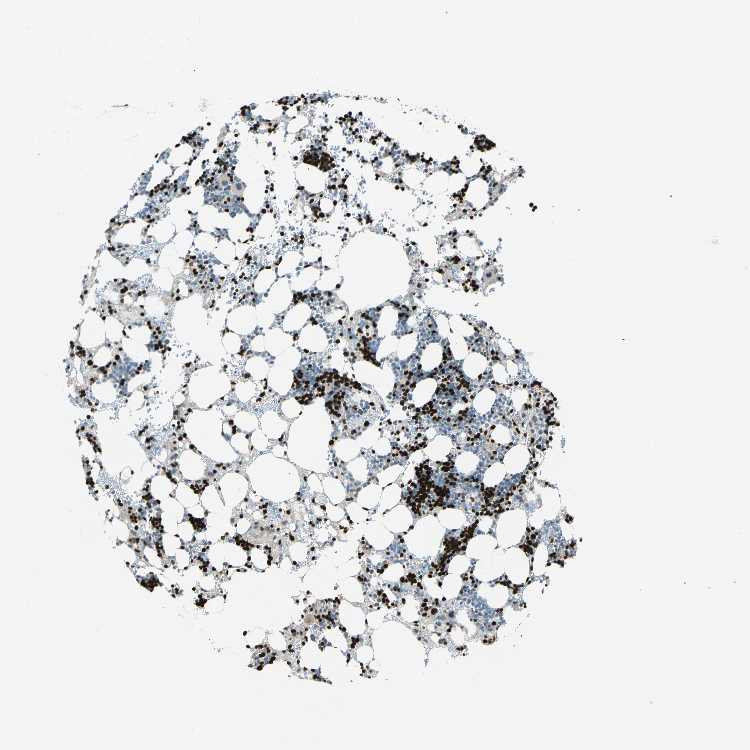

BONE MARROW - Antibody stainingi

Antibody staining in the annotated cell types in the current human tissue is reported as not detected, low, medium, or high, based on conventional immunohistochemistry profiling in selected tissues. This score is based on the combination of the staining intensity and fraction of stained cells.

Each image is clickable and will lead to virtual microscopy that enables deeper exploration of all samples and also displays staining intensity scores, fraction scores and subcellular localization as well as patient and tissue information for each sample.

Antibody HPA006111Antibody HPA008884

Hematopoietic cells HighHigh